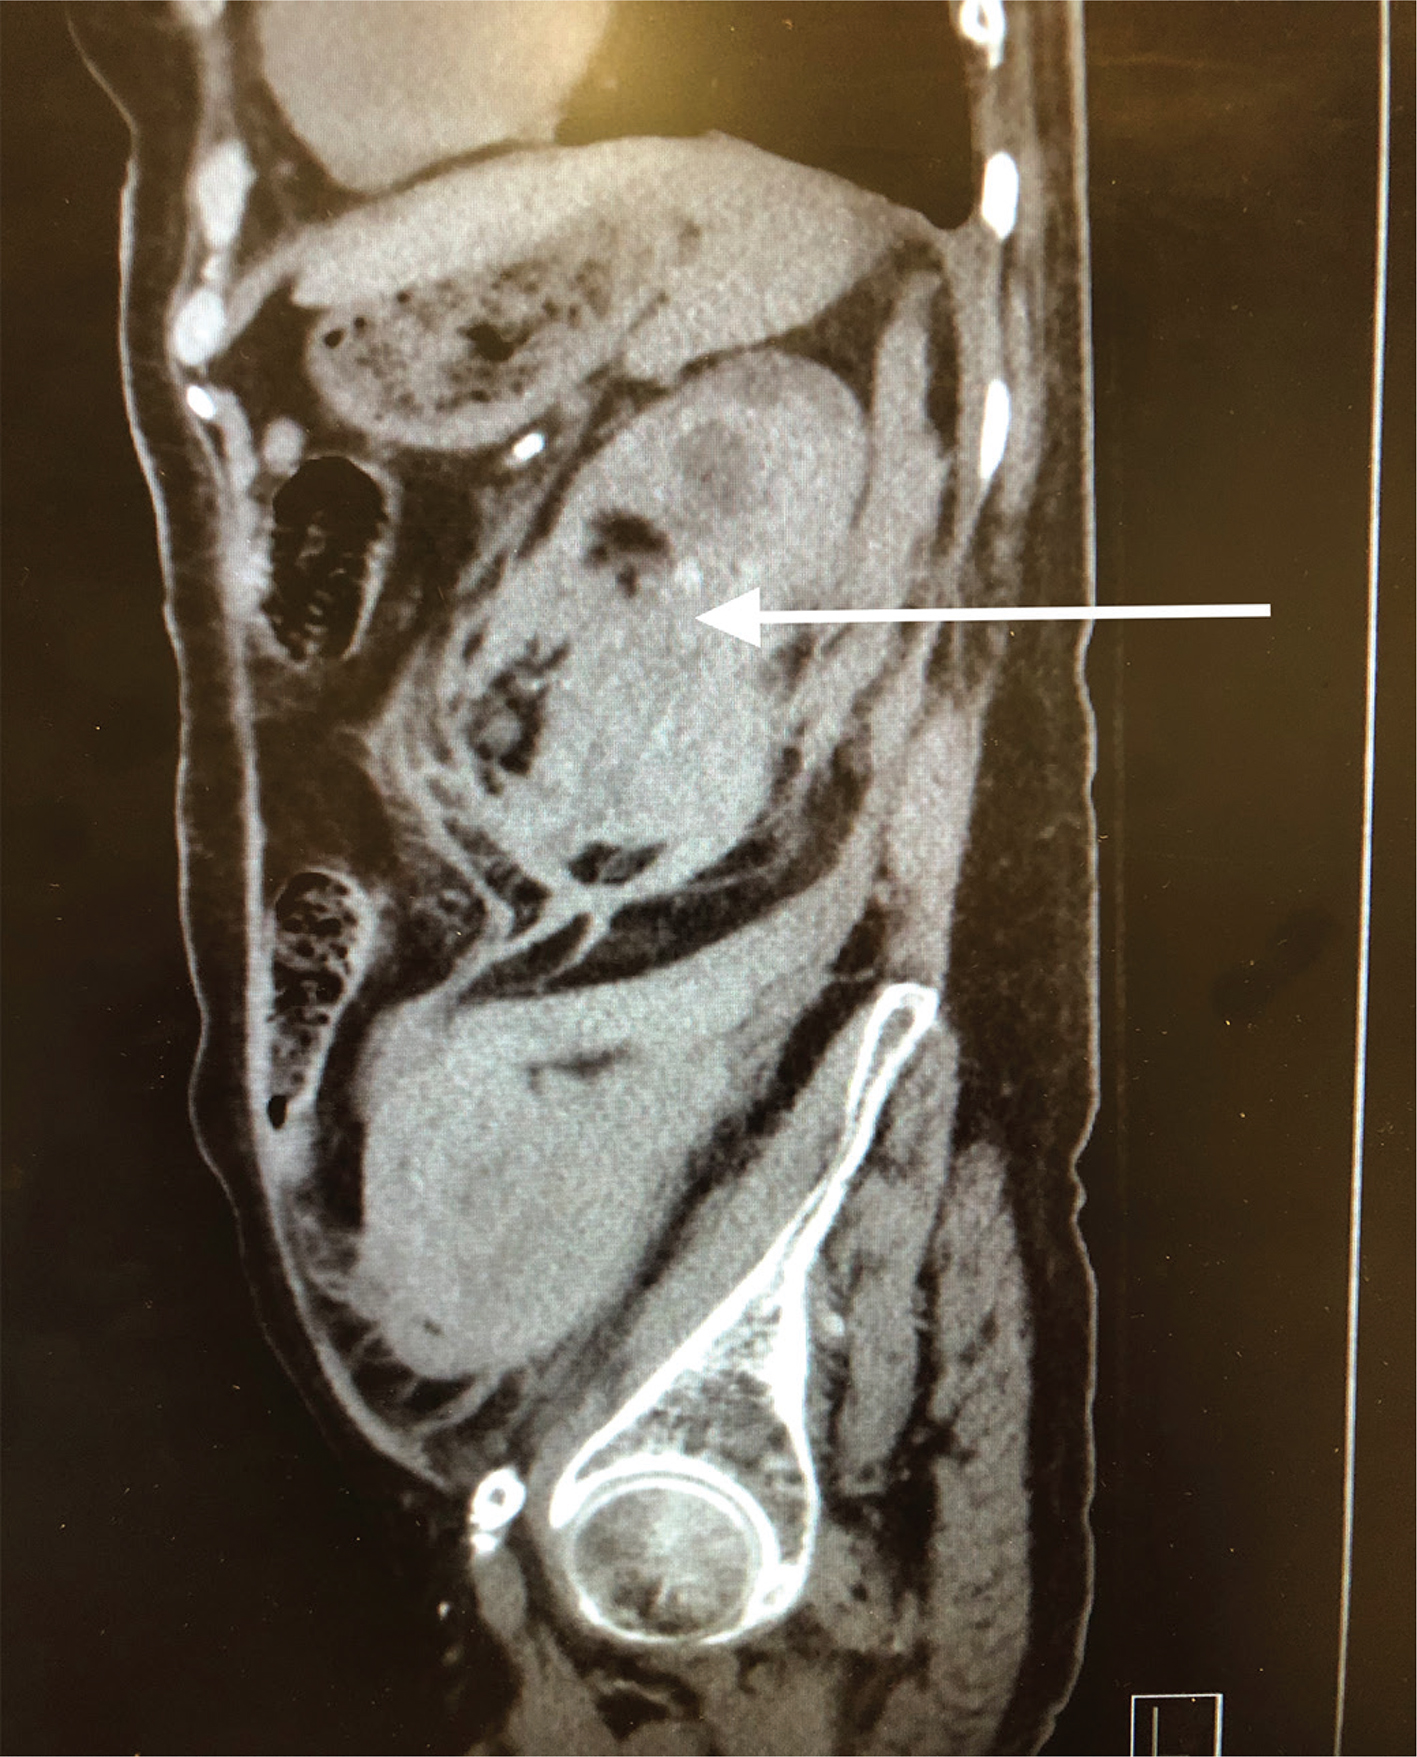

Pathology showed extensive sclerosed glomeruli, marked interstitial inflammation, severe arteriosclerosis, perirenal and renal parenchymal hemorrhage, severe renal artery atherosclerosis, and ACKD. Figurers 1 and 2 show the enlarged left kidney with massive retroperitoneal hemorrhage on CT scan.

Figure 2: Sagital CT image of left retroperitoneal hemorrhage. The arrow shows the extensive left retroperitoneal hematoma with rupture of the left kidney.